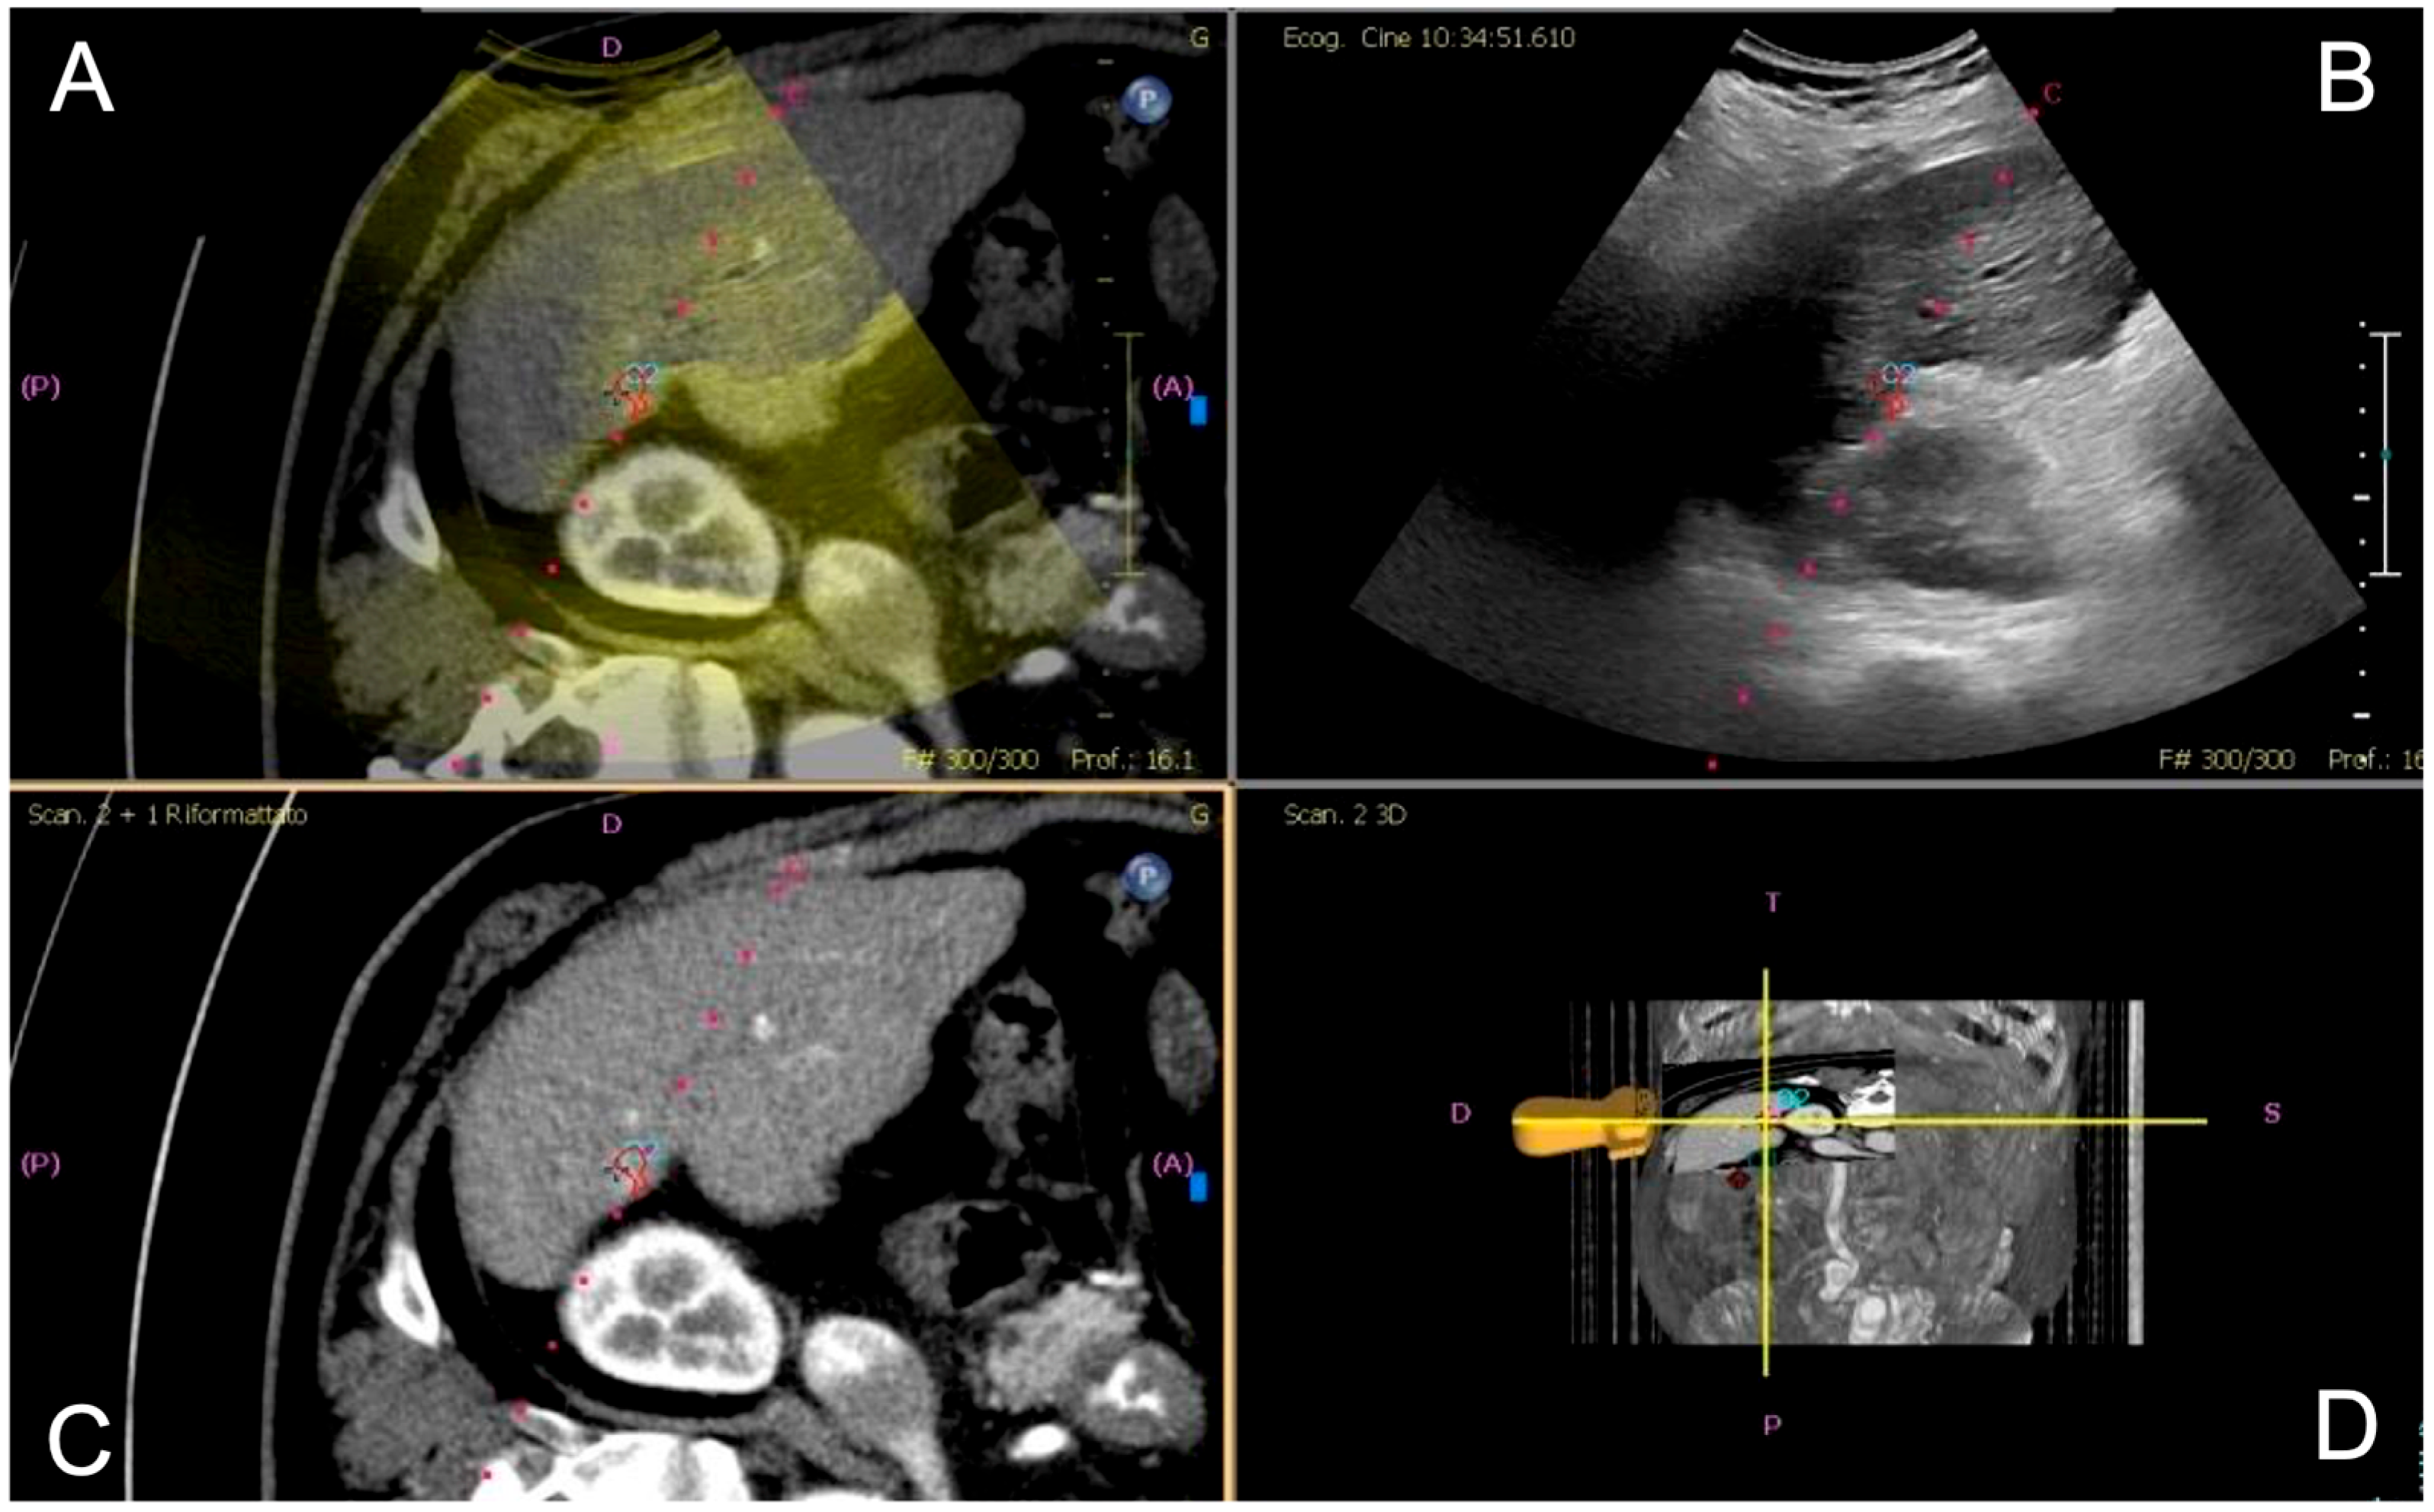

Fusion imaging was performed with electromagnetic tracking using automatic vessel registration via dedicated software (PercuNav System, Software vers. 7.0.8, Philips Medical Systems, Netherlands).The process involves acquiring an ultrasound scan of the liver to create a 3D dataset registered by a software to cross-sectional images based on the hepatic vessels (Figure 1). If automatic registration was not judged adequate, some manual adjustments were performed.

Figure 1. Image fusion workflow for percutaneous ablation planning. After co-registration of pre-procedural CT images with real-time ultrasound (US), the integrated display includes: fused CT–US images with the US superimposed on the CT images (A), real-time US alone (B), CT images alone (C), and 3D position of the US probe (D). The target lesion is highlighted with a pink circle, aiding in precise localization for intervention.